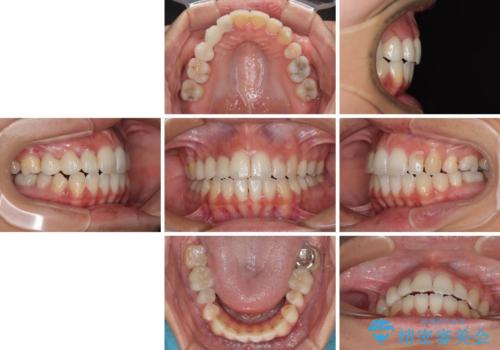

開咬と前突を改善 ワイヤー装置での抜歯矯正

結果として下顎の小臼歯は抜歯せず、右上の抜歯スペースはむし歯処置を兼ねてオールセラミックブリッジにて補綴治療を行うこととしました。

動かない歯での停滞や、出産と子育てなどにより治療期間は長期化しましたが、整った歯列にて仕上げることができました。